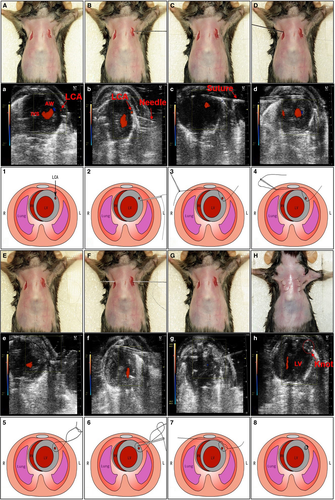

摘要:急性心肌梗死(MI)是世界上发病率和死亡率的主要原因。传统的左冠状动脉(LCA)结扎诱导心肌梗塞的方法通常是通过一种需要开胸的侵入性方法进行的,这会导致接受此手术的动物受到严重伤害。我们试图开发一种微创方法(MIM)诱导小鼠心肌梗死。在超声引导下,对无通气和开胸的小鼠进行LCA结扎。与假手术组小鼠相比,氯化三苯基四唑染色和Masson染色检测MIM诱导的小鼠心肌梗死。. MIM手术的小鼠在术后24小时显示LVEF、LVFS、E/A和升主动脉(AAO)血流减少,S -T段和血清cTn-I水平升高。MIM诱导心肌梗死的作用与传统方法对小鼠心肌梗死的作用相当。重要的是,与传统方法相比,MIM提高了LCA结扎术后的生存率,减少了炎症。此外,与传统方法一样,MIM诱导小鼠术后28天缺血性心脏的血管生成和凋亡。最后,MIM模型可以通过一个气囊导管修改发展成心肌缺血/再灌注模型。在无通气和开胸的情况下,通过微创方法可以有效地诱导小鼠心肌梗死模型。这一新模型有可能用于研究缺血性心脏病。简介:缺血性心脏病由动脉粥样硬化、高血压和血管僵硬等引起,是世界范围内的主要死亡原因。急性心肌梗死(MI)是缺血性心脏病最常见的表现形式,是发病率和死亡率的主要原因。为了了解基础医学研究中的病理生理过程和治疗策略,如硝酸盐耐受性、易损斑块、侧支动脉形成和内皮功能障碍,需要一个高效、损伤小的心肌梗死动物模型。Johns和Olson于1954年首次提出了一种基于通气的开胸术,通过结扎小鼠左主降支(LCA)建立心肌梗死模型,其中许多手术操作都是为了诱发心脏缺血事件。尽管LCA结扎仍然是最常见的缺血损伤,但其仍需采用需要通风和完全打开胸部的方法,导致广泛的组织损伤和高手术相关死亡。然而,这种方法也需要迅速打开胸腔,因为如果胸腔关闭,LCA是看不见的。开胸手术可能会造成一些创伤,不仅会增加动物疼痛和死亡,还会对全身免疫同态性产生一些有害影响,这种情况限制了与人类患者的临床相关性。在这项研究中,我们建立了一种新的方法来诱导小鼠心肌梗塞而不打开胸腔和不通气。在超声辅助下进行的该微创方法(MIM)包括LCA的识别、经胸穿刺和LCA结扎。与传统的小鼠心肌梗死诱导方法相比,新方法可降低小鼠术后死亡率和炎症反应。此外,我们还将该模型应用于小鼠缺血再灌注损伤的新模型,这表明该手术具有广泛的应用前景。不开胸永久性冠状动脉闭塞方案:所有药物浓度均表示为缓冲液中的最终摩尔浓度。雄性野生型(C57BL6)小鼠,8~12周,20~25g。1、用干珠消毒器消毒手术器械。2、小鼠(一般为2-3个月大或至少18 g)吸入2%-3%异氟醚进行麻醉。3、麻醉后,将小鼠移到手术板上,用胶带固定,通过呼吸装置连续用2%异氟烷麻醉。4、用标准脱毛剂(如Nair)脱毛,用水清洗皮肤,然后用聚维酮碘和酒精消毒。为了更有效地执行此步骤,可以更早地执行脱毛。5、用剪刀在胸部左右两侧皮肤上做两个小切口(0.5厘米长),以暴露第三肋间间隙。6、进行超声心动图检查。超声心动图探头垂直于第三肋间空间内的胸部矢状面,成像左心室(LV)短轴。图1a所示为超声下的LCA。在左胸第三肋骨上缘肋角处插入一根直径为0.2毫米的小直针。当它到达LCA的下方时,我们轻轻地按压8-0丝线连接的针尖,让针尖向上移动一点。在超声波的引导下,心脏表面被直针刺穿,针头从右胸穿出皮肤。然后,从右到左将针插回原位。当针头穿过心脏时,它会在超声波的作用下通过LCA上方,从左胸的同一部位穿出皮肤。针只通过轻轻按压缝合线两侧来扩大空间,穿过胸部前壁和心脏前壁之间的空间。打一个松结,针就从左到右插回胸部。LCA现在位于绳结内部。小心拉动缝合线两端,结扎LCA。在超声波下很容易看到绳结。心电图(S-T段抬高)的典型缺血改变证实了结扎。如果MIM手术期间未观察到S-T升高,则应排除动物。假手术组除了LCA没有被阻塞外,进行同样的手术。在切口闭合后立即皮下注射丁丙诺啡(0.1 mg/kg)。用PBS和酒精清洗手术工具。心电图分析:如前所述,使用电生理记录系统记录 CICAL手术前后的心电图定量。在整个CICAL和CICAL I/R过程中,还记录了超声心动图成像系统心电图的变化。简言之,在超声心动图上,将电极与三只小鼠肢体皮肤连接,以监测心电图的变化。血浆cTn-I水平的测量:小鼠在手术后24小时被处死。ELISA试剂盒检测血清CTN-I水平。Microfil造影剂被注射到左心室,直到它积聚在冠状动脉中。完成后,取出灌注器官,放入多聚甲醛中数小时。图像是在徕卡M205 FC立体显微镜上获得的。手术后24小时迅速切除心脏,然后在冷PBS中清洗三次。心脏从心尖沿长轴横向切成1.0毫米厚的切片。横切面在1%的TTC的磷酸盐溶液(pH7.4)中37°C下孵育20分钟,然后转移到10%福尔马林中,在室温下孵育20分钟。图像是由普通照相机拍摄的。Masson三色染色法评价心肌损伤:小鼠在心肌梗塞手术后24小时和4周被处死。心脏在室温下用4%多聚甲醛固定过夜,依次用乙醇、正丁醇脱水,石蜡包埋。纵向切片(4μm)用Masson三色染色。在全景MIDI上采集图像,并通过Image-Pro Plus软件计算心肌梗死面积。梗死面积是指所有心脏切片上梗死所占的心外膜和心内膜周长的百分比。体内超声心动图测量:麻醉后,将单个小鼠置于加热垫(37°C)上,并使用带有超声心动图探头的VEVO 2100微超声系统进行超声心动图检查。利用声像分析软件计算和记录了左室射血分数和左室射血分数的百分比变化、左室射血分数的峰值速度(Vmax)、E和A峰值。免疫组织化学法测定血管生成:对术后28天从小鼠收集的灌注心脏进行组织学分析。然后切开右心房,灌注心肌血管,然后用10%福尔马林灌注10分钟。心脏在4%福尔马林中固定24小时。将福尔马林固定组织嵌入石蜡中,切成4μm的切片。为了测量毛细血管密度(计数/mm2),我们进行了CD31的免疫组化分析。细胞凋亡分析:用4%多聚甲醛固定组织。通过末端脱氧核苷酸转移酶介导的dutp末端标记(tunel)染色评估细胞凋亡。细胞凋亡的百分比是根据TUNEL阳性细胞数除以细胞总数计算得出的。结果:新型MIM成功地建立了小鼠心肌梗死模型:我们采用了新的方法来诱导心肌梗死损伤而不需要通气和开胸。为了确定这种新方法是否有效地诱导心肌梗死,我们使用microfil 血管造影对心脏和冠状动脉进行了可视化,并检查了心肌梗死的大小,如前所述。在所有用于MIM手术的63只小鼠中,2只小鼠在手术后6小时内死于LCA血管闭塞,3只小鼠被排除在外,因为在MIM手术期间未观察到S-T段抬高。我们没有观察到主要并发症,如气胸。microfil 血管造影清楚地勾勒出了LCA,用MIM手术在小鼠心脏上结扎。microfil 血管造影成像也能清楚地识别心肌梗死区域。还通过TTC染色和Masson三色染色检查心肌梗死面积。Masson三色染色定量分析表明,MIM新方法可导致小鼠显著的心肌缺血。这些结果表明,新的MIM成功地诱导了无通气和开胸的小鼠心肌梗死模型。MIM术后小鼠血清CTN-I水平升高:急性心肌梗死是由缺血引起的心肌肌钙蛋白I(CTN-I)升高,因此,我们检测血清cTn-I水平,进一步证实MIM诱导心肌梗死的作用。与假手术组相比,术后24小时血清CTN-I水平明显升高,提示该方法可有效诱导小鼠心肌损伤。新方法诱导小鼠心功能不全:心功能不全是导致心肌梗死患者死亡率的一个关键因素。然后,我们通过术后24小时心电图(ECG)检查心肌梗塞对MIM手术小鼠心脏功能的影响。与假手术小鼠相比,MIM手术小鼠的S-T段明显抬高。此外,MIM小鼠的LVEF 和LVFS均下降,提示新方法引起的心脏前壁运动受损。通过计算升主动脉(AAO)血流量的Vmax和E/A峰比值,确定心脏的收缩和舒张功能。与假手术后的小鼠相比,MIM手术后的小鼠AAO的Vmax和E/A峰比值均明显降低,表明该方法是诱发小鼠心脏功能障碍的有效方法。MIM手术缩短了恢复时间,减少炎症:为了评价MIM手术后的损伤程度,我们比较了新方法与传统方法对小鼠术后恢复时间的影响。恢复时间定义为从手术完成到动物意识或运动恢复的时间间隔。新方法假手术组恢复时间比传统方法假手术组恢复时间明显缩短。传统的心肌梗死手术恢复时间比传统的假手术恢复时间长,但新方法假手术组同新方法MI手术组恢复时间无明显差异,提示在MIM手术中LCA结扎不会导致小鼠过度受伤。为了研究新方法引起的炎症反应,我们在术后24小时测量了TNFα和IL-6的血浆水平。与未经手术的小鼠相比,传统方法和新方法均显著提高了TNFα和IL-6的血浆水平。与假手术小鼠相比,传统的心肌梗死手术方法进一步提高了TNFα和IL-6的血浆水平,而新方法则没有。总的来说,上述数据表明,新的手术造成的组织损伤较小,手术后恢复更快。MIM手术新方法诱导血管生成:MI后血管生成对于重建存活心肌的血液供应,从而恢复心脏功能至关重要。为了验证该模型是否适用于研究血管生成,我们通过分析内皮细胞的生物标志物CD31来检测血管生成。传统方法和新方法均能显著诱导心肌梗塞小鼠的血管生成,表明该方法适用于研究心肌梗塞诱导的血管生成。MIM手术新方法诱导心肌细胞凋亡:研究也证实了凋亡在缺血性心脏病中的重要作用,导致心肌细胞死亡和左心室重构。为了验证该模型是否适用于心肌梗死诱导心肌细胞凋亡的研究,我们用TUNEL检测了心肌细胞凋亡。与假手术小鼠相比,传统方法和新方法均能使缺血区心肌细胞凋亡率完全升高。结果表明,MIM手术与传统的研究缺血诱导血管生成的方法一样有效。新方法建立的MI模型在I/R模型中的应用:I/R模型通常用于检查缺血损伤的短期后果,并已用于研究创新心脏保护疗法的发展。在新方法基础上进行了改进建立了I/R模型。在结扎LCA之前,我们在结内放置了一个球囊导管。通过给球囊充气45分钟并连续放气3小时,我们轻轻地将球囊导管从胸部取出。伊文斯蓝加TTC染色显示缺血的AAR和左心室的梗死面积表明,MIM手术成功地在小鼠体内产生了一个I/R模型。此外,基于MIM的I/R组和传统I/R模型组的MI大小相同。结果表明,改进的MIM手术方法可用于小鼠I/R损伤的研究。结论:我们有效地建立了一个无需开胸和通气的微创心肌梗死模型。这一新模型不仅适用于研究缺血诱导的血管生成和凋亡,而且进行微小的修改还可发展为I/R模型。